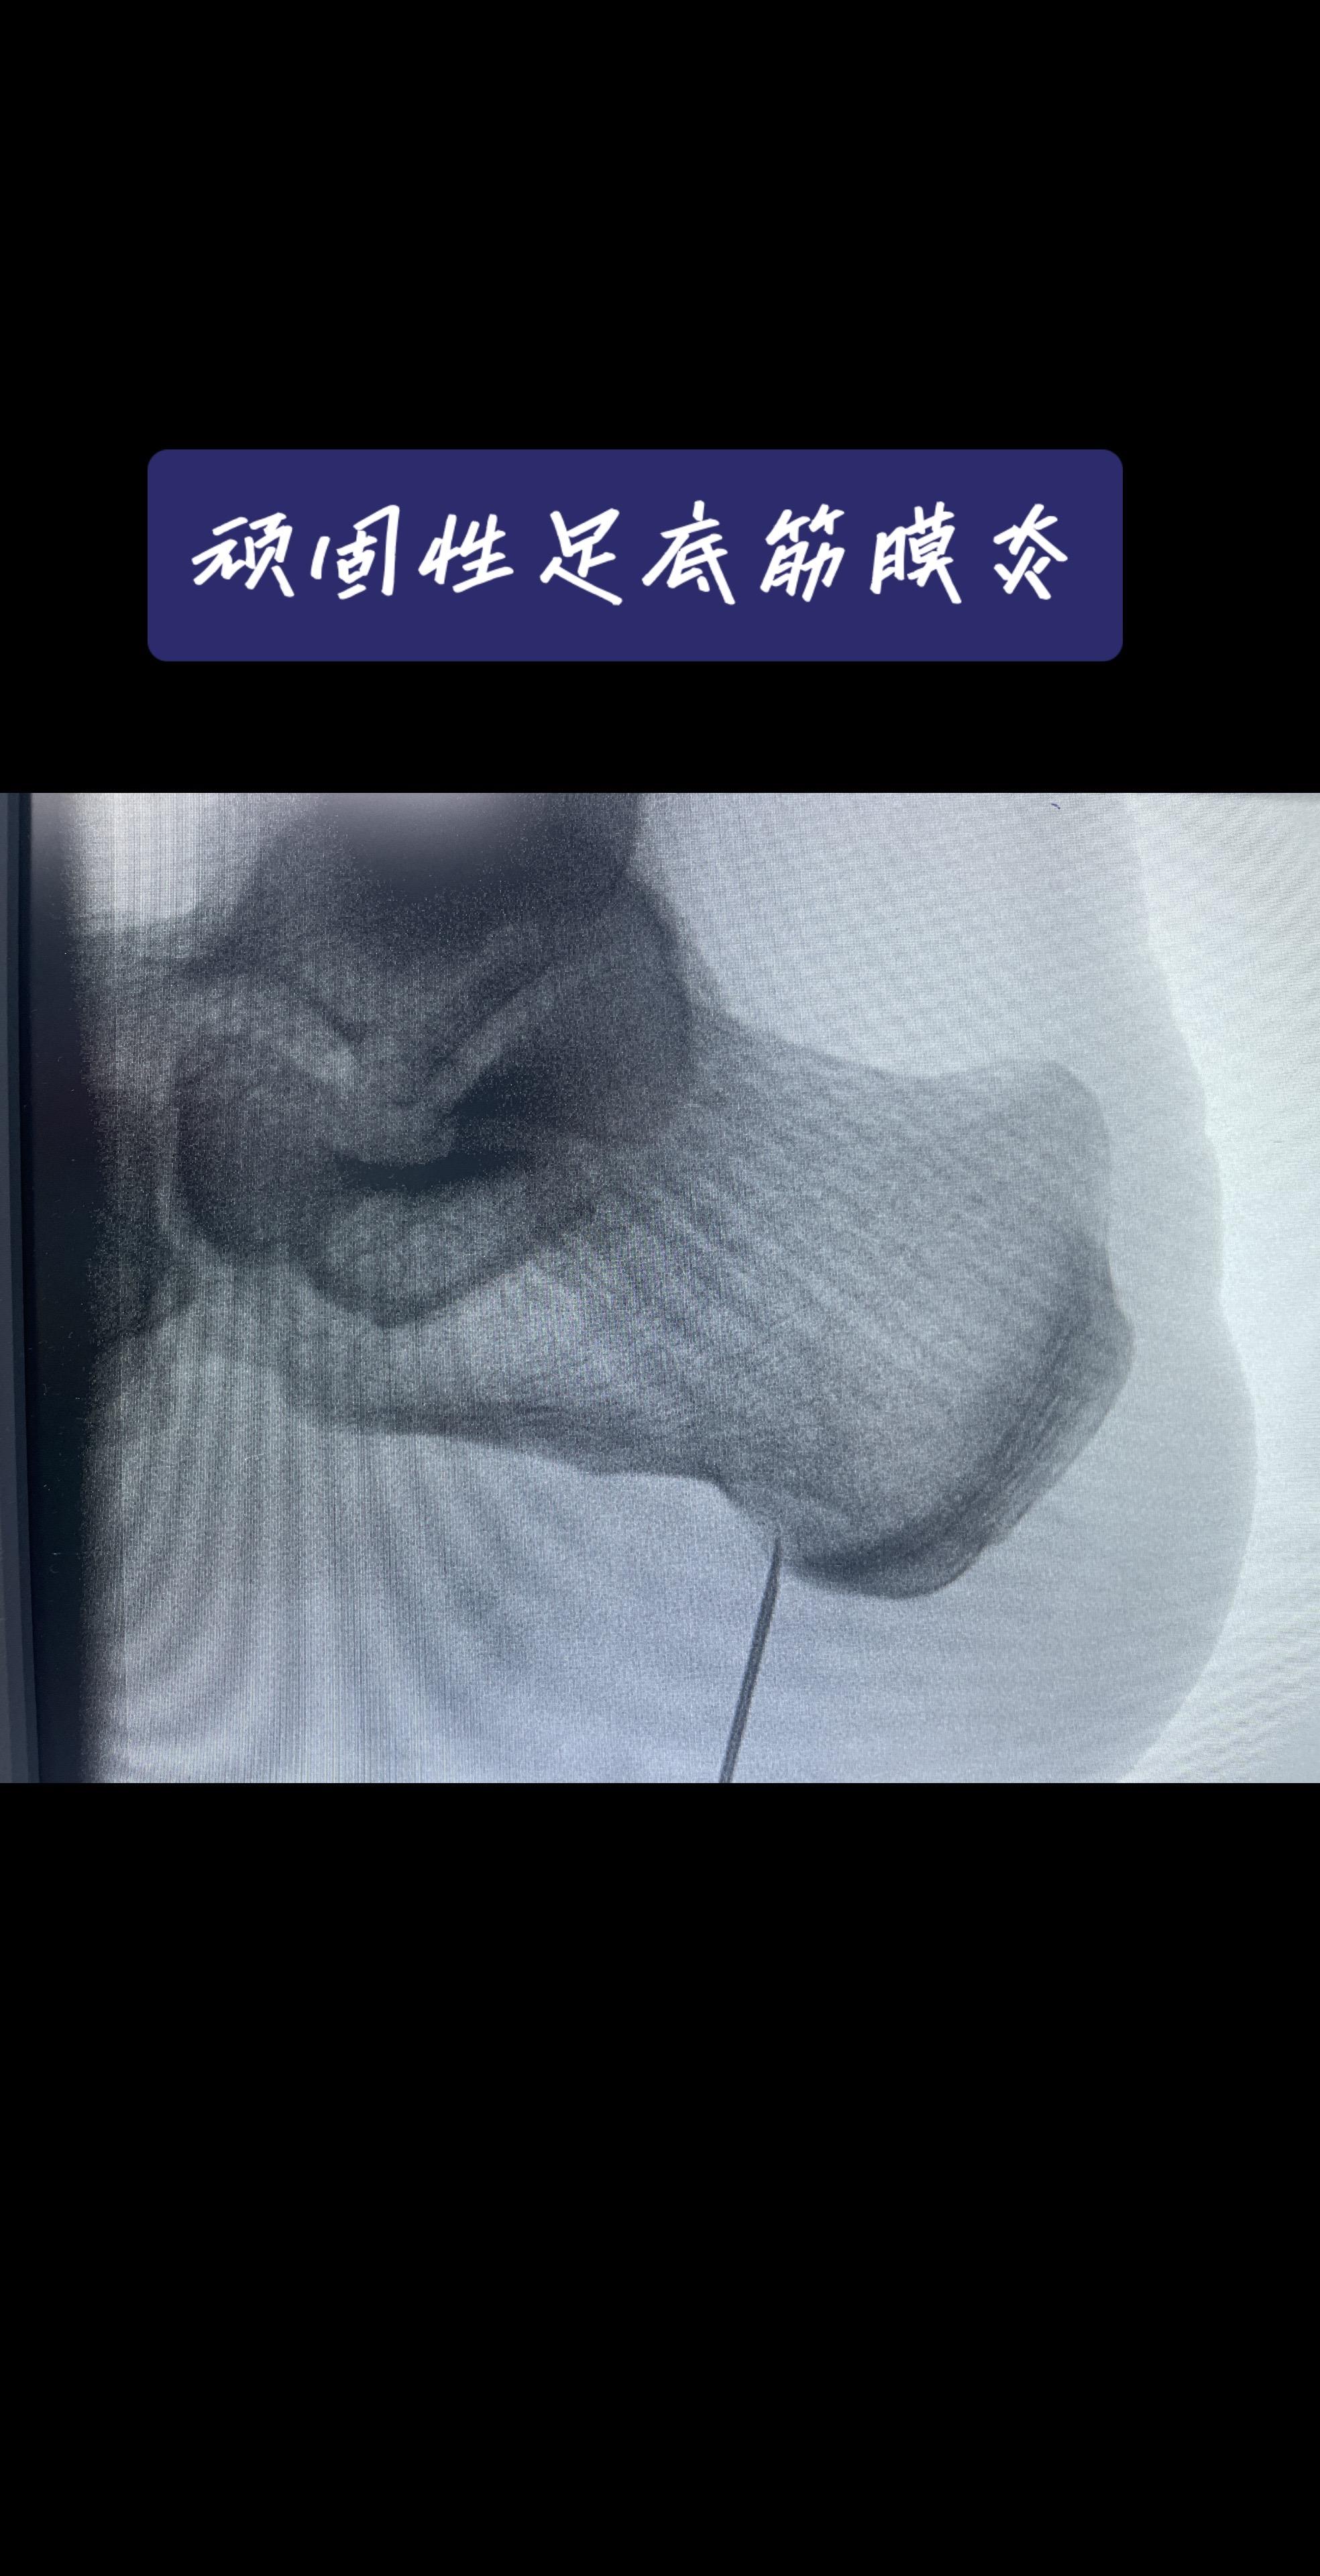

脚后跟像踩针?一走路就钻心疼?对于忍了好几年,试遍各种方法都没用的‘顽固分子’,我们怎么办?——关节镜下的‘筋膜松解术’,创伤小、恢复快,告别‘起步痛’!